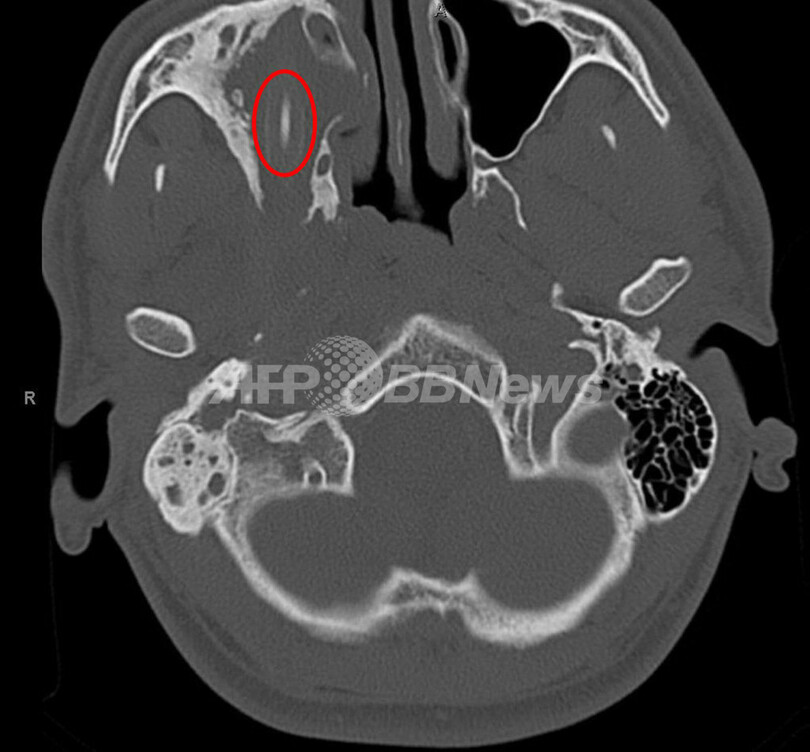

【5月30日 AFP】ドイツで、視力障害や頭痛を訴えていた男性(24)の頭の中から、子どもの頃に入り込んだとみられる鉛筆が発見され、無事摘出されていたことが分かった。

アフガニスタン出身のこの男性は、右目の視力障害や頭痛、右の鼻孔から出る膿(うみ)といった症状を訴えていた。鉛筆がどうやって頭の中に入ったのかは男性にもよく分からないが、15年ほど前の少年期に、転んで鼻から激しく出血したことを覚えていたという。

医師らが行ったCTスキャン(コンピュータ断層撮影)の結果、喉の奥に刺さった長さ7センチの鉛筆により、眼窩(がんか)が傷つけられていることが分かった。摘出手術の後、男性は迅速に回復したが、視力には障害が残ったという。(c)AFP/Hasbanullah Khan